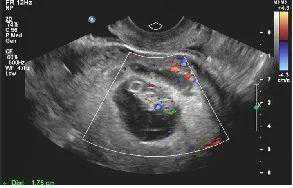

【一超二超照片】

二超

2019年10月29日二超:宫腔内见胚囊,大小31*21*31mm,胚芽长18mm,胎心167次/分。二超当天顺利毕业,转往产科建卡!